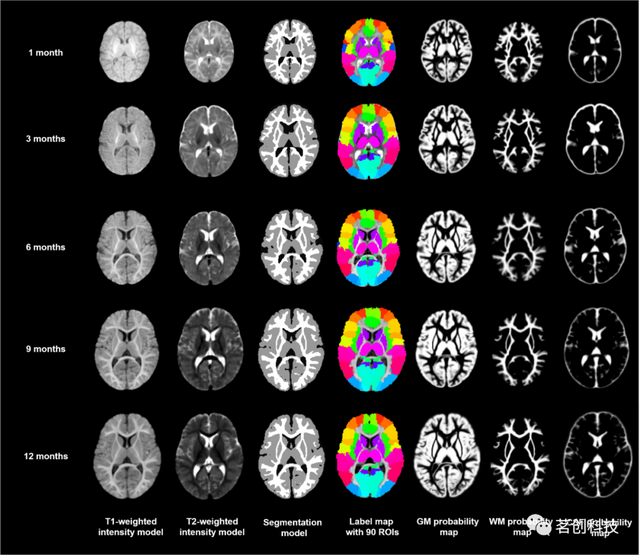

UNC纵向0-3-6-9-12个月大的婴儿图谱

这是一组典型的0、3、6、9和12个月大的婴儿时空图谱,由35名健康婴儿组成,这些婴儿每三个月进行一次纵向扫描,直到一岁。该图谱由组平均T1和T2加权图像组成,其中包括灰质、白质和脑脊液的组织概率图。其主要意义在于同时引入了时间和空间约束,以生成具有丰富结构细节和纵向一致性的图集。纳入了3个月、6个月和9个月的图谱有助于分析婴儿MRI,因为在生命的第一年,大多数大脑区域的灰质和白质之间的T1和T2加权对比度仍然很差。

下载地址:

https://www.nitrc.org/projects/infant_atlas_4d/

来源:Consistent spatial-temporal longitudinal atlas construction for developing infant brains.